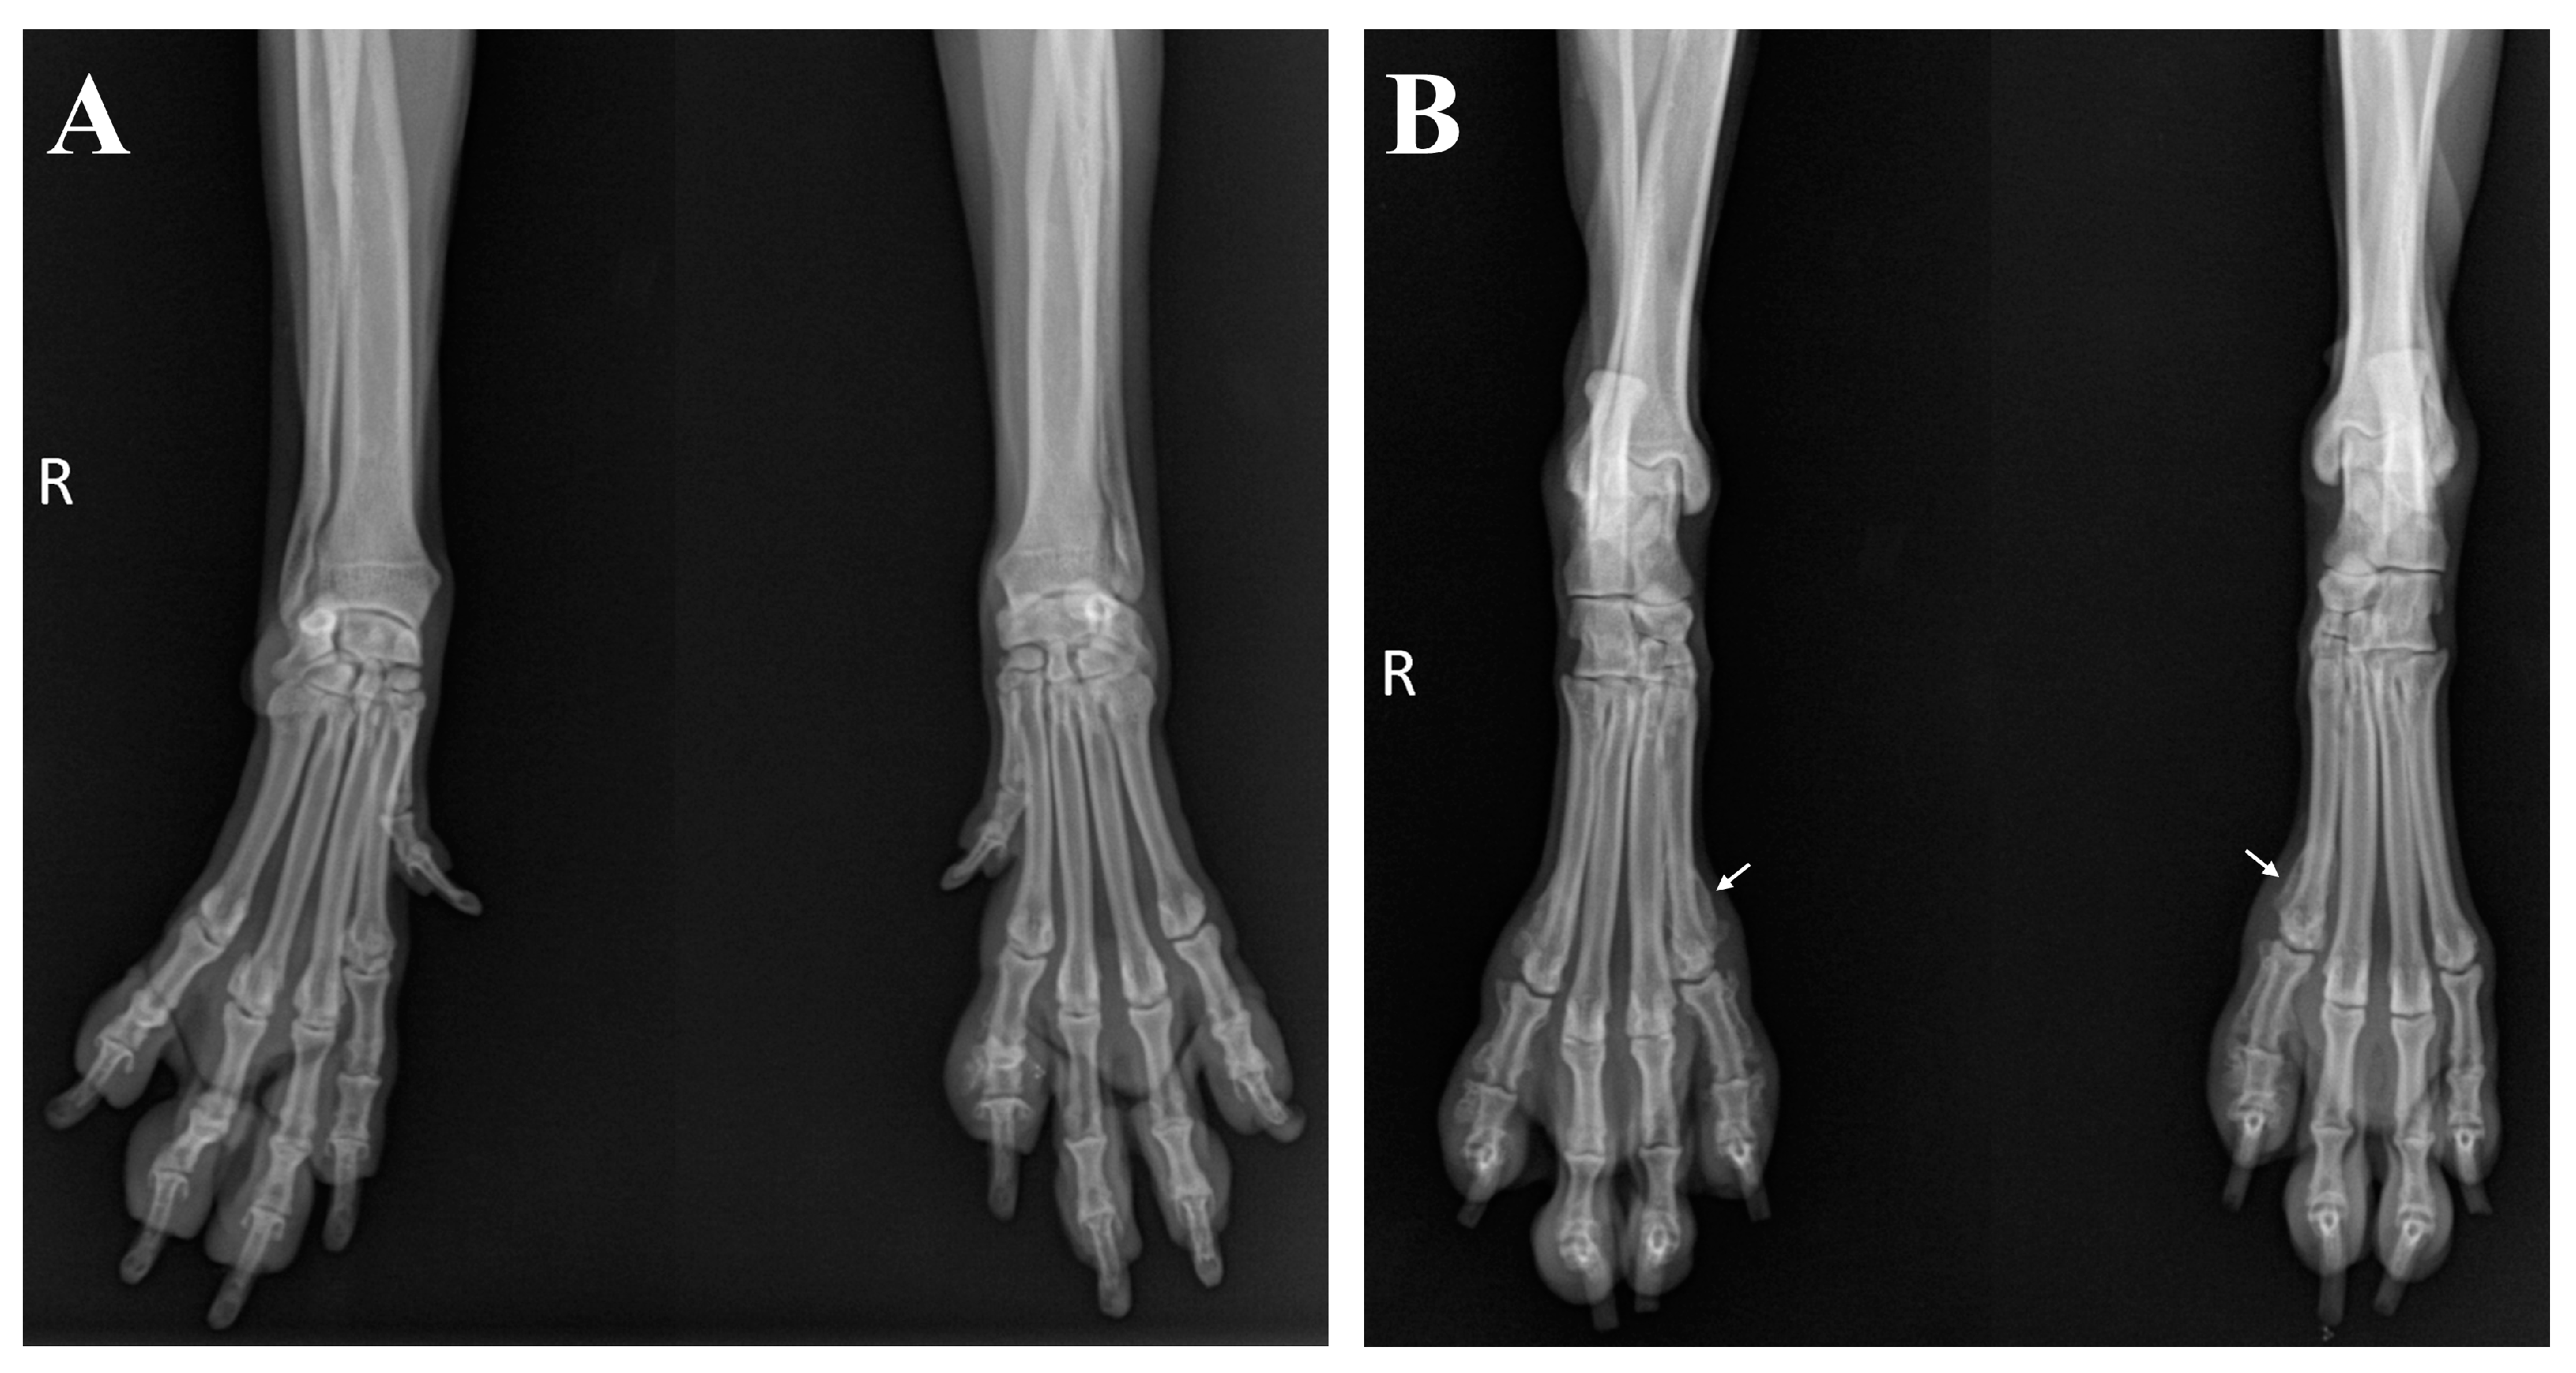

2. Case Description

3. Diagnostic Assessment, Intervention, and Outcomes